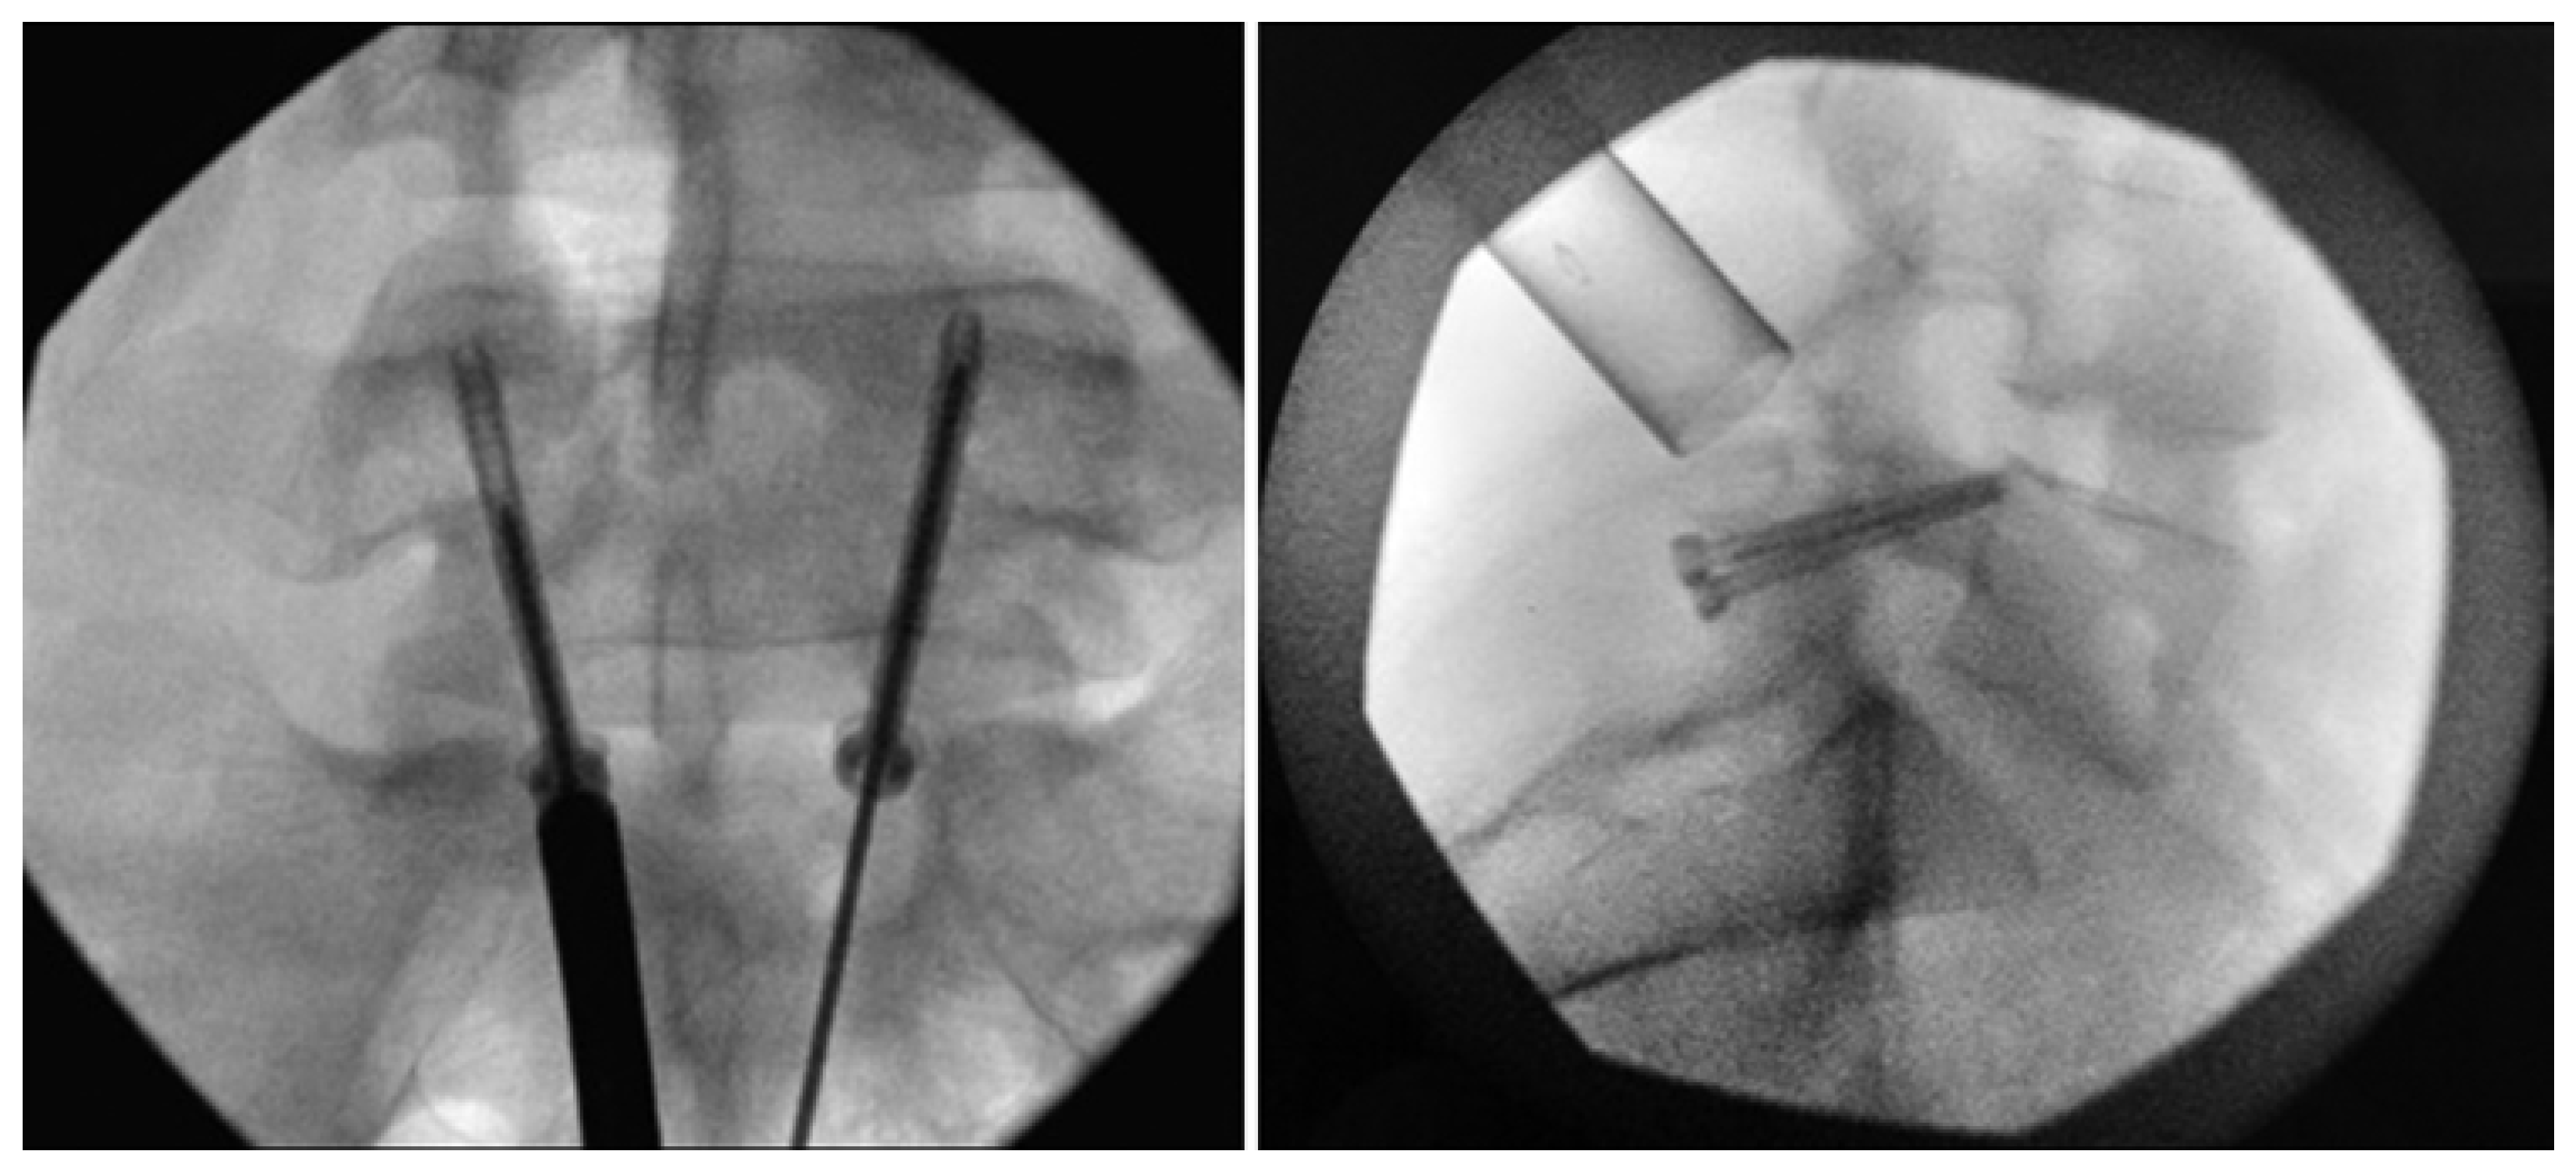

Levi Technique—Minimally Invasive Direct Pars Screw Placement

- Widi, G.A.; Williams, S.K.; Levi, A.D. Minimally invasive direct repair of bilateral lumbar spine pars defects in athletes. Case Rep. Med. 2013, 2013, 659078. [Google Scholar] [CrossRef]

- Ghobrial, G.M.; Crandall, K.M.; Lau, A.; Williams, S.K.; Levi, A.D. Minimally invasive direct pars repair with cannulated screws and recombinant human bone morphogenetic protein: Case series and review of the literature. Neurosurg. Focus 2017, 43, E6. [Google Scholar] [CrossRef] [PubMed]